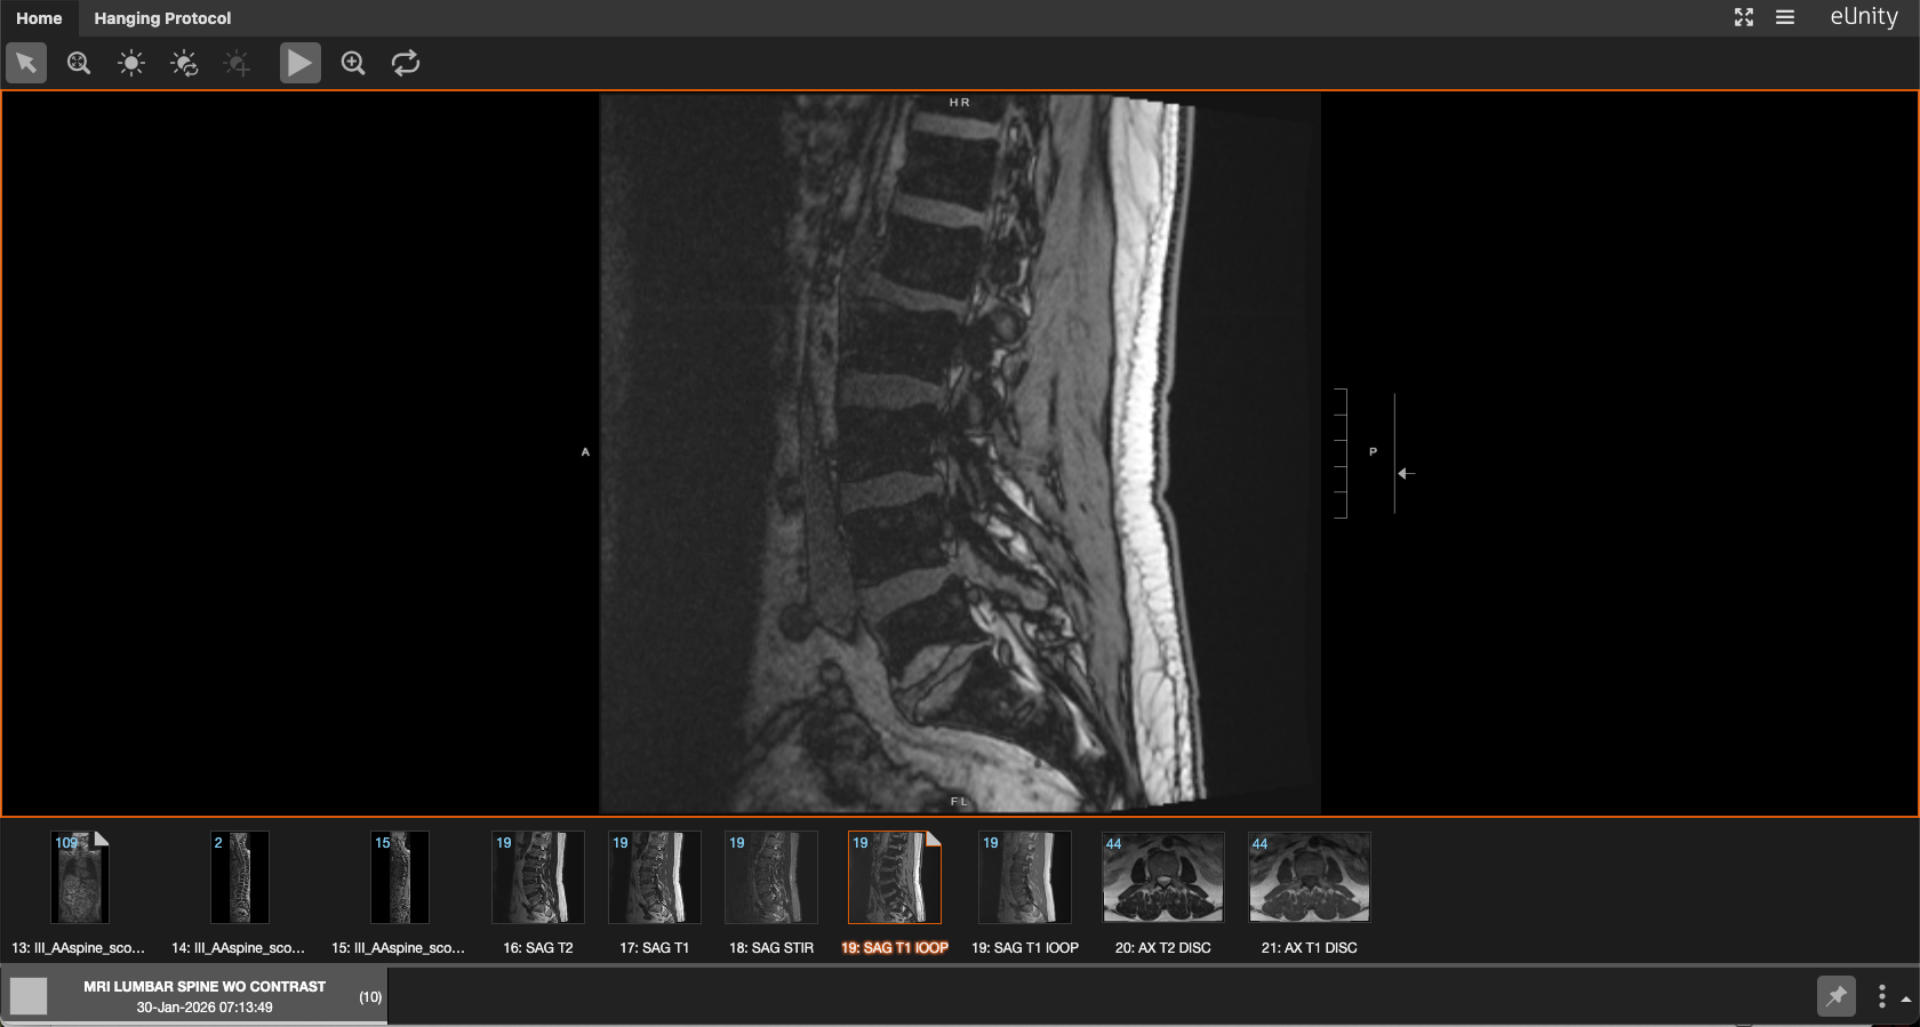

Oh! A lot has happened since the last post. I saw a doctor, got an injection in my hip (that did not work and offered no relief) and then I got an increase in my medication, and then I got an MRI and then another increase in my medication (sigh) and sometimes I have to take out-of-state medication.

So what’s next? Well, I got an EMG (electromyography) and the good news is my nerves are not damaged. So I saw another doctor this week and we’re going to move forward with getting me two injections into each side of my spine because they can’t do just one from the back due to the spacing. (Eww.)